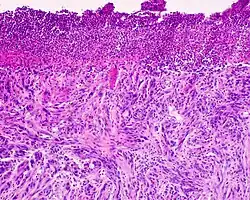

Desmoplastic melanoma, also known as neurotropic melanoma, or spindled melanoma[1] is a rare cutaneous condition characterized by a deeply infiltrating type of melanoma[2]: 696 with an abundance of fibrous matrix. It usually occurs in the head and neck region of older people with sun-damaged skin. Diagnosis can be difficult as it has a similar appearance to sclerosing melanocytic nevi as well as some nonmelanocytic skin lesions such as scars, fibromas, or cysts. Desmoplastic melanomas tend to recur locally, with distant metastasis being less common.[3]